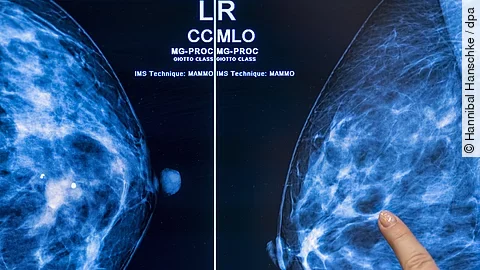

Bei der Untersuchung wird ihre Brust geröntgt, um Veränderungen so früh wie möglich zu erkennen. Damit soll die Zahl der Brustkrebs-Todesfälle gesenkt werden. Zudem soll den betroffenen Frauen eine möglichst schonende Behandlung ermöglicht werden. Brustkrebs ist bei Frauen mit Abstand die häufigste Krebserkrankung. Laut aktuellsten Daten des Zentrums für Krebsregisterdaten am Robert Koch-Institut gab es 2022 bundesweit 74.500 Neuerkrankungen bei Frauen.